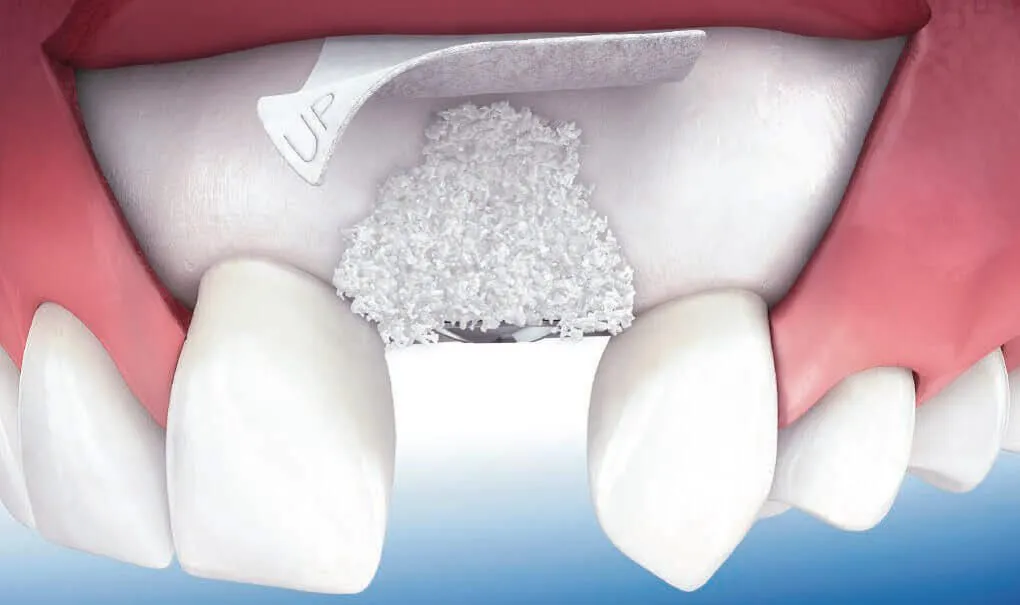

Ghép xương răng là kỹ thuật nha khoa khá phức tạp, nhằm mục đích tăng thể tích và tăng độ cứng cho xương hàm khi thực hiện cấy ghép răng Implant. Trước khi tiến hành cấy ghép, nha sĩ sẽ chụp x-quang để đánh giá chất lượng xương hàm và chỉ định cấy ghép phù hợp. Để hiểu rõ hơn về kỹ thuật này và biết được những trường hợp nào cần cấy xương răng, hãy cùng theo dõi bài viết này của Nha khoa Dr Green.

Cấy xương răng là kỹ thuật bổ sung xương vào hàm, nhằm mục đích tái tạo và làm tăng thể tích của xương hàm, tăng độ rắn chắc, giúp nâng đỡ trụ Implant khi trồng răng giả cố định.

Kỹ thuật này sẽ được thực hiện trước khi đặt trụ Implant khoảng 9 – 12 tháng, để đảm bảo xương mới tương thích và ổn định trong cơ thể. Khi xương đã đủ cứng chắc, bạn sẽ được tiến hành đặt trụ Implant và thực hiện các bước tiếp theo.

Đối với kỹ thuật cấy xương hàm, hiện có 4 phương pháp phổ biến nhất được thực hiện, bao gồm:

- Ghép xương tổng hợp: Đây là vật liệu tổng hợp gần giống với xương tự nhiên, có thành phần chính Calcium Phosphate.

- Ghép xương dị chủng: Đây là xương tự nhiên lấy từ một loài động vật khác, đã được kiểm tra về độ tương thích.

- Ghép xương tự thân: Lấy trực tiếp xương trong cơ thể của bệnh nhân để thực hiện cấy ghép.

- Ghép xương đồng chủng: Lấy xương từ cơ thể người khác, đã được kiểm tra về độ tương thích.